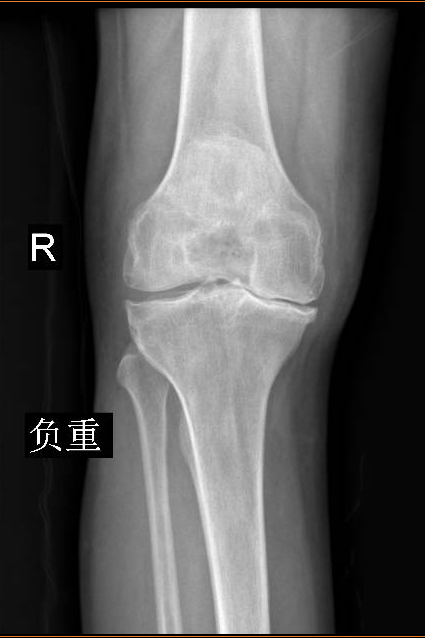

2020年1月初,程珂琳副主任醫師在門診見到了老Tim,看到他一瘸一拐艱難地走進診室,程醫生發現老Tim的病情比想象中還要嚴重。經過認真地詢問病史、查體,結合影像檢查,老Tim被確診為老年性雙膝骨性關節炎,程醫生表示可以通過手術有效緩解疼痛,并且配合術后的康復治療,患者能恢復正常行走。完善了相關檢查以后,1月10日,老Tim住進了關節骨病科,并于次日接受了手術治療。手術由關節骨病科、麻醉科等科室共同完成,程珂琳副主任醫師及其團隊僅用1個小時就成功地為老Tim實施了人工膝關節表面置換術,手術快而精準。

術前